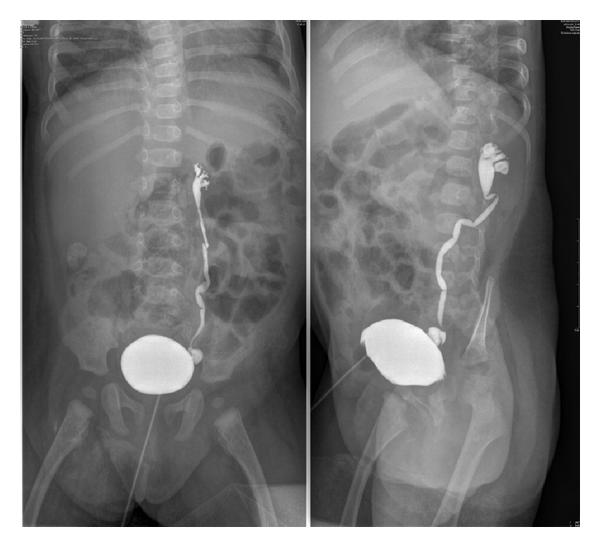

what’s used to diagnose vesicoureteral reflux? us is normal

voiding cystourethrogram